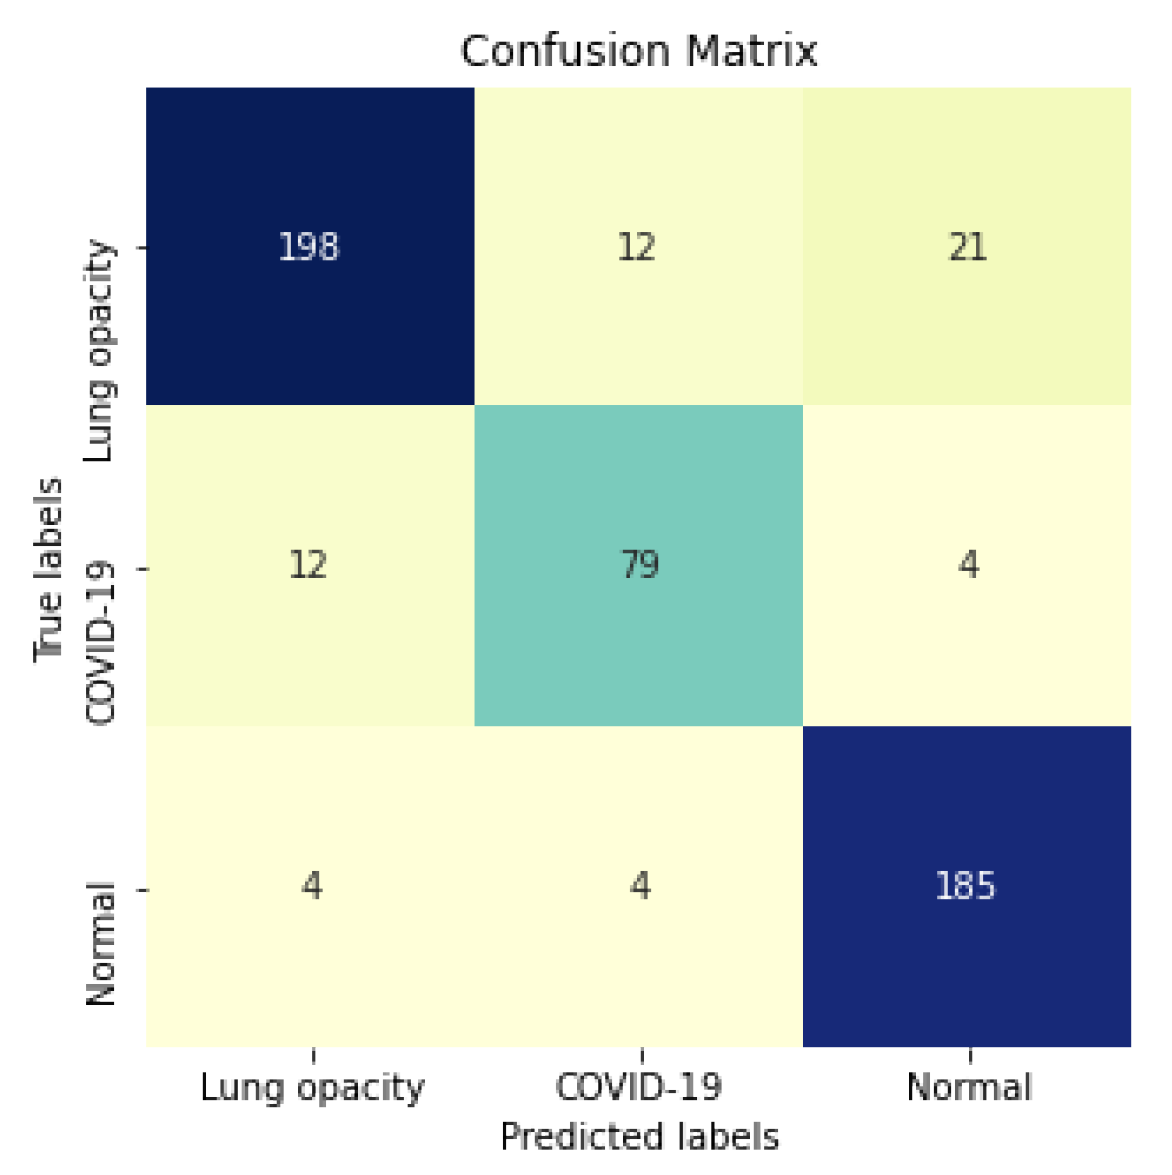

Considering specifically the models using segmented CXR images, InceptionV3 performed better in all classes.

Figure 15 shows the confusion matrix for the InceptionV3 using segmented CXR images. Overall the classifier presented a remarkable performance in all labels. The largest misclassification happened with the class Lung opacity being predicted as Normal, followed by the class COVID-19 being predicted as Lung opacity. However, there are reasonable explanations for both: (i) Most examples from the classes Lung opacity and Normal came from the RSNA database; thus, we believe that the data source biased the classification marginally; (ii) pneumonia caused by COVID-19 could have been confused with pneumonia caused by another pathogen. A solution for both issues would be to increase the number of images in the database, including more data sources.